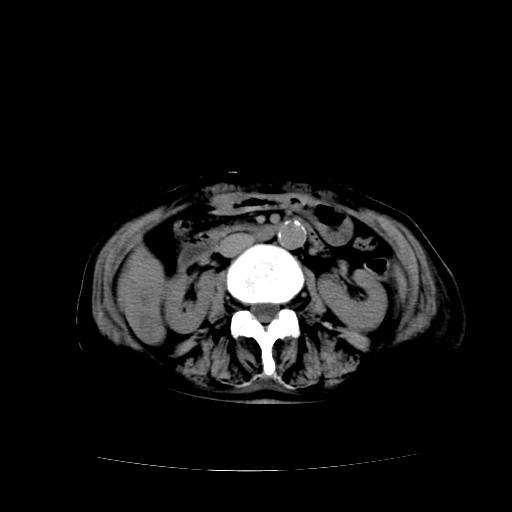

标题: CT17152:女70Y乳腺CA

女70y乳腺ca(针吸活检)

多部位转移瘤的诊断可以肯定,我的疑问是:双肺对称高密度影及胸水是否为心衰肺水肿,病人体虚弱,不好意思图象传的乱![em9]

1)左侧乳腺癌并左侧腋窝及纵隔淋巴结转移,两肺淋巴道转移(癌性淋巴管炎),肝脏多发性转移。2)双侧胸腔积液。3)慢性胆囊炎。

1)左侧乳腺癌并左侧腋窝及纵隔淋巴结转移,肝脏多发性转移。2)双侧胸腔积液伴双肺蝶翼样磨玻璃高密度影,双侧肺门血管影增粗(图像不全,肺门层面没纵隔窗),考虑心功能不全所致。3)慢性胆囊炎伴壁钙化。